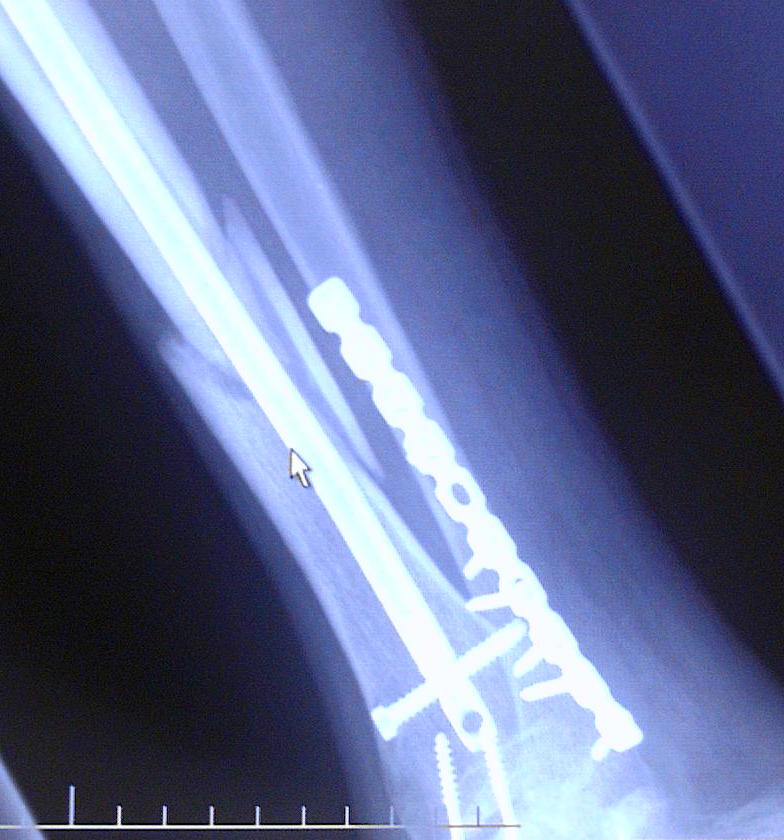

This is Diesel's X-ray's from 9-30-04. He broke hiz tibula on June 21, 2004 doing a 12 o'clock wheelie. Clutch slipped and he flipped over the handle bars and landed ALL hiz weight on hiz right leg causing it to snap.

He just got hiz 3rd cast removed and found out that the bone is not progressing. He now has an walking cast on with a bone stimulator (to maximize circulation to that area) which he will most likely have for the next 6 months. As you can see in the X-Ray's he has a metal plate on the anterior side of hiz ankle where he broke it in 2 places. You can see where the tibula broke and how it is not healing. He has 13 screws and a titanium rod throughout the tibula. Price you pay for being a Stunter!

He just got hiz 3rd cast removed and found out that the bone is not progressing. He now has an walking cast on with a bone stimulator (to maximize circulation to that area) which he will most likely have for the next 6 months. As you can see in the X-Ray's he has a metal plate on the anterior side of hiz ankle where he broke it in 2 places. You can see where the tibula broke and how it is not healing. He has 13 screws and a titanium rod throughout the tibula. Price you pay for being a Stunter! "INSANE STUNTERZ"